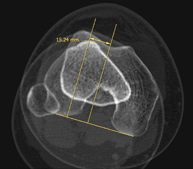

- TC d'estudi rotacional EEII (Bàscula rotuliana, distància TA-GT) Exploració radiològica que mitjançant un sistema de raigs X i detectors que giren al voltant del pacient i que reconstrueixen les imatges per ordinador (TC Multidetector), permet calcular una sèrie de mesures a nivell de maluc, genolls i turmells per solucionar problemes de rotació i angulació de les extremitats inferiors. Exploració radiològica que mitjançant un sistema de raigs X i detectors que giren al voltant del pacient i que reconstrueixen les imatges per ordinador (TC Multidetector), permet calcular una sèrie de mesures a nivell de maluc, genolls i turmells per solucionar problemes de rotació i angulació de les extremitats inferiors.